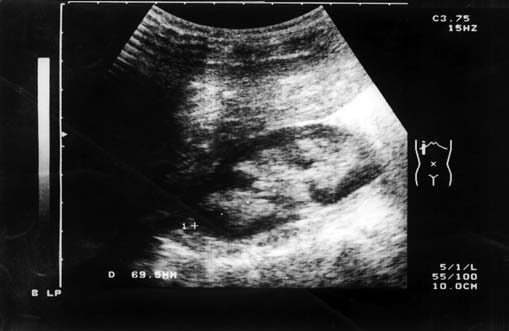

A 3-year-old boy was referred for evaluation of proteinuria during a febrile illness.He had no history of edema, hematuria, or polyuria.Physical examination revealed no abnormal findings. His weight was 17.2 kg and his height was 1 m . His blood pressure was 80/50 mmHg. Funduscopic examination was normal.Laboratory investigation revealed +2 protein, no blood,and normal urine sediment, blood urea 23 mg/dl, serum creatinine 0.45 mg/dl, calcium 8.9 mg/dl, phosphorus 3.5 mg/dl, sodium 139 mEq/l, potassium 4.1 mEq/l, bicarbonate 26.4 mEq/l, cholesterol 180 mg/dl, total protein 7 g/dl, albumin 3.5 g/dl, hemoglobin 11.6 g/dl, white blood cell count 8,700/mm3, platelet count 366,000/mm3, aspartate amino transferase 34 U/l, and alanine amino transferase 16 U/l. Urine protein excretion was 630–945 mg/24 h.Renal ultrasonography showed marked bilateral medullary hyperechogenicity suggestive of medullary nephrocalcinosis. Urinary calcium excretion ranged between 4.6 and 5.3 mg/kg per 24 h.His maternal grand father had died at 57 years of age in end stage renal disease. He had been undergoing hemodialysis for 4 years, but the etiology of his renal disease was not clearly defined. He died from cardiovascular causes. There was no parental consanguinity.

Medullary nephrocalcinosis is present in most patients. Some patients also develop calcium nephrolithiasis. Rickets occurs in about a third of the patients. The cause of the rickets is unknown. There is usually no hypocalcemia or acidosis. Some patients develop hypophosphatemia,but this has not been considered severe enough to explain the bone disease.